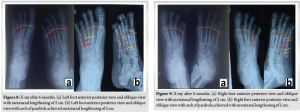

A 21-year-old female patient complained of deformity of both feet since her childhood associated with pain. The patient had undergone conservative modalities, such as orthotics, medical treatments, and insoles. The patient took physiotherapy with lifestyle modifications but had no pain relief. The patient felt that her feet were esthetically unpleasing (Fig. 1a and b). The patient was clinically evaluated and had shortening of bilateral fourth toes (Fig. 1a and b), tenderness over the bilateral fourth metatarsal ray, cock-up deformity over bilateral fourth toes, and sulcus sign over the plantar aspect of bilateral fourth toes. The patient had no comorbidities. The patient was evaluated for any associated syndromes and found to be negative. Pre-operative blood investigations and anesthesia fitness for surgery were obtained. A pre-operative plan was made using a bilateral foot X-ray. Anteroposterior and oblique views showed a 2-cm shortening in both fourth metatarsals (Fig. 2a, b) and a 5-mm shortening of the bilateral proximal phalanx (Fig. 2a, b) and malalignment of the Lelièvre parabolic arch[10] (Fig. 2c). A diagnosis of congenital bilateral brachymetatarsia of the fourth metatarsal was made. The patient was planned for lengthening of bilateral metatarsals using distraction osteogenesis with an external rail fixator[11,12].

The patient’s primary complaint of pain was treated as the parabolic arch of the metatarsal head (Fig. 8a, b and 9a, b-b) was restored, along with a lengthening of 2 cm. After removal of the external fixator (Fig. 10a, b, c, d), the patient was pain-free and functionally restored.